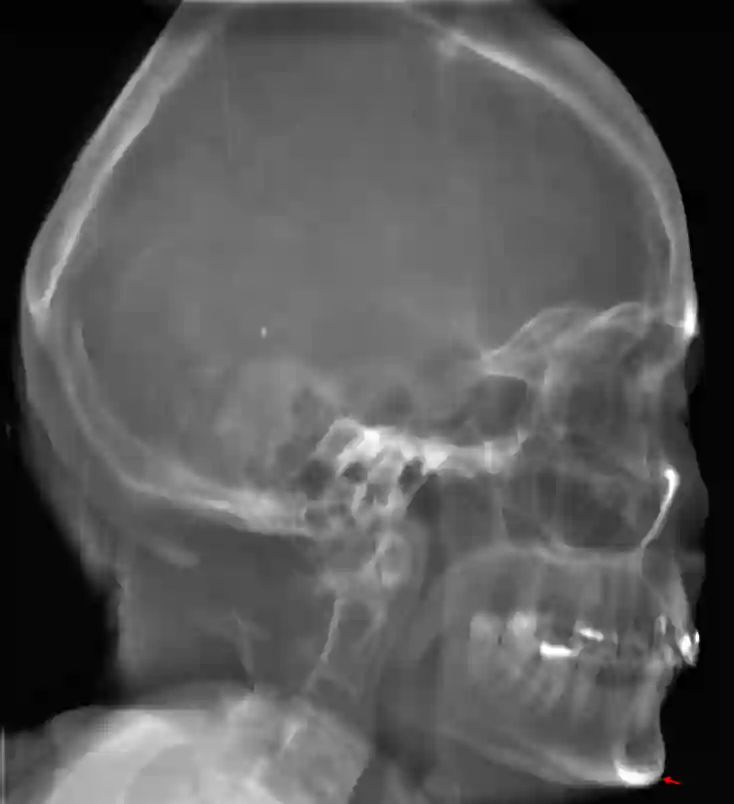

Das Gnathion oder auch als Menton bezeichnete Punkt ist der in der Mediansagittalebene am weitesten vorstehende Punkt des Mandibula-Unterrandes.

Darstellung des Gnathion in einer lateralen Röntgenaufnahme des Schädels.